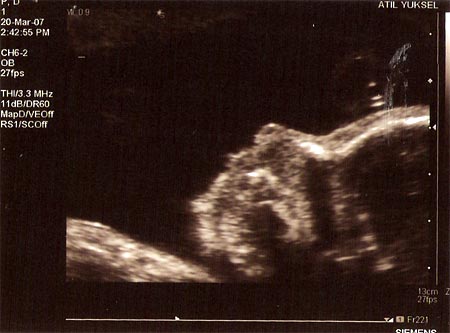

Yukarıda Atıl Yüksel’in muayenehanesinde yapılan detaylı ultrasondan görüntüler var. Yaklaşık 10 fotograftan en anlaşılır olanları. (Anlaşılır derken kimin için anlaşılır olduğu tartışılır tabi) Diğer fotograflarda da kalp, cigerler, damarlar, kol bacak neyin her bir şey var, biz çok bir şey anlamasak da doktorlar anlıyor elbet. Yukarıdaki fotografların ikisinde kızımızın yüzünü profilden görmek mümkün. Ortada ise eli var. (Detaylı ultrasonda yarık dudak, yarık damak, eksik parmak gibi sorunlara bakılıyor, yukarıdaki fotograflar da o esnada çekildi…)

Bu durumda kızımızın bir eli başının altında uyuklarken çekilmiş fotografı hala en net, en yüzü görülür, şekli şemali anlaşılır fotograf olma özelligini koruyor. Bir sonraki ultrasonumuz 20 Nisan’da, dolayısıyla daha net ve etli butlu fotograflar için daha bekleyeceğiz.

(Yukarıdaki fotografları daha büyük açmak için üzerlerine tıklamanız yeterli)